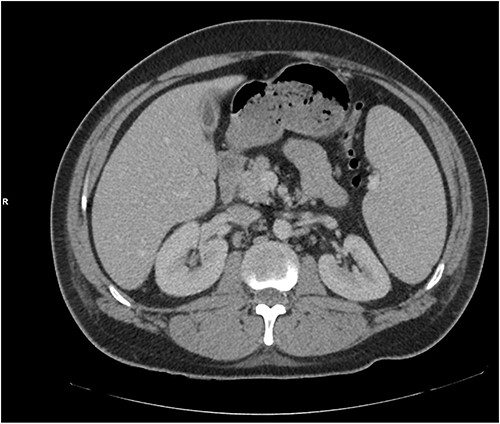

The patient was treated with IV piperacillin-tazobactam. However, he continued to have febrile temperature spikes. No growth was initially detected on blood cultures. The patient developed shortness of breath and respiratory alkalosis, for which a CT pulmonary angiography was done to exclude pulmonary embolism. Only dependent bilateral changes in the lower lobes and signs of mild pulmonary venous congestion were reported (Fig. 3). He was started on hydrocortisone, ethambutol, pyridoxine and rifampicin as empirical treatment for BCGosis. Hydrocortisone was eventually tailored down to prednisolone. Virology tests including hepatitis and immunodeficiency virus were run and these were negative. He continued spiking high temperatures and a repeat CT abdomen with IV contrast was performed which was largely unchanged from the previous scan (Fig. 4). An echocardiogram ruled out infective endocarditis. Incidentally he was in contact with a COVID-19 positive patient and was placed under quarantine for 14 days. Fortunately, he never developed COVID-19 infection. Another CT pulmonary angiography was performed in view of persisting shortness of breath but only mosaic attenuation in the lungs was present.

A repeat CT abdomen with IV contrast was performed which was largely unchanged from the previous scan, save for mild pericholecystic fluid.